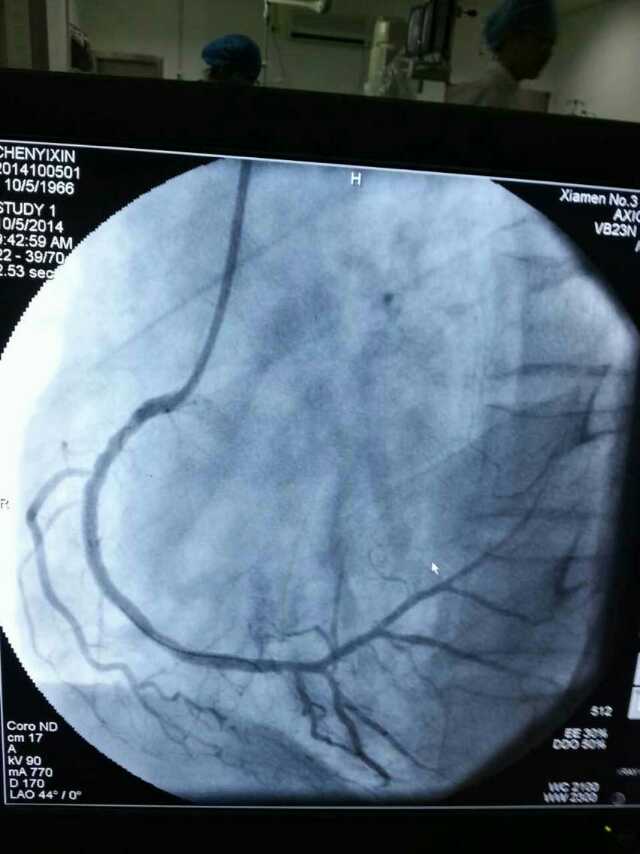

3月20日,家住翔安的庄先生为感谢91club 心血管内科的医护人员在第一时间对他的病情给予明确诊断,并及时采取有效治疗措施,让他的心脏病很快得到康复回家。特地送来一面写着“德医双馨,妙手回春”锦旗以表达他们满满的感激之情。